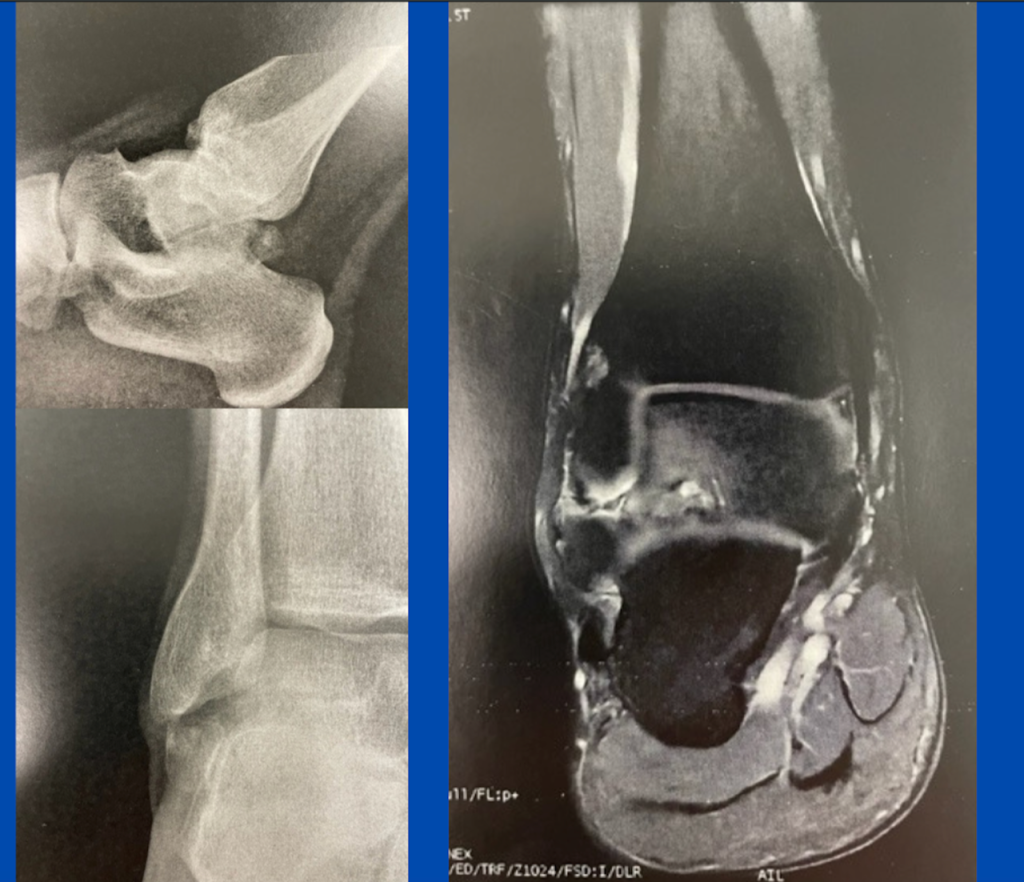

Blog's main page These are intra-operative images taken during the surgery to remove the painful ossicles discussed in my previous article, Posterior "ankle pain" Note how large the removed bones are. The os trigonum had been particularly painful as it was large and had fractured during the initial trauma, plus it was pushing against the flexor [...]

Blog's main page This active 25-year-old has presented with marked "ankle pain" following all activities. He remembers a severe inversion sprain when he was a child and informs me he has had a corticosteroid injection into the ankle joint with no success. There are 3 very specific regions of pain: the anterior lateral ankle the posterior [...]